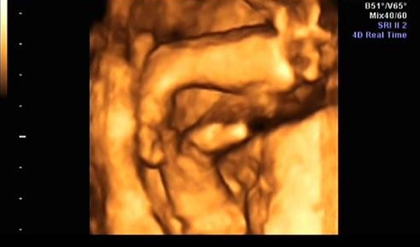

四维报告单子上的名词都有哪些意思?

股骨长(FL):大腿的长度,也叫大腿骨长,这是身体中最长的一部分的数值。用于和BPD(胎头大横径)一起来推算胎儿的体重。

肱骨长(HL):胎儿上臂骨的长度,肱骨长度=-5.4282+0.7542×双顶径。